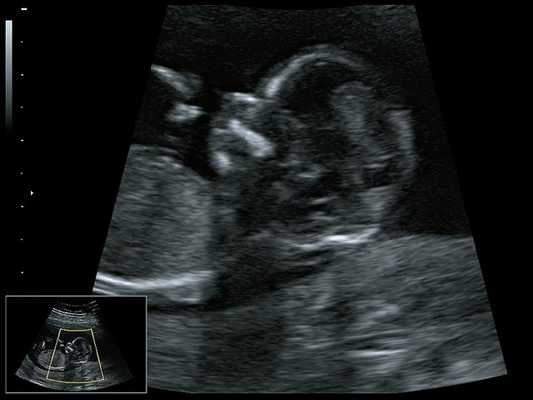

При ультразвуковом исследовании выявлены множественные особенности лицевого фенотипа у плода: микрогнатия (рис. 2–4), треугольная форма лица (рис. 5), опущенные книзу глазницы и гипоплазия скуловых дуг (рис. 6, 7), аномальная форма и положение ушей (рис. 5, 7).

Рис. 2. Микрогнатия - сагиттальный скан в 2D, беременность 13 нед.